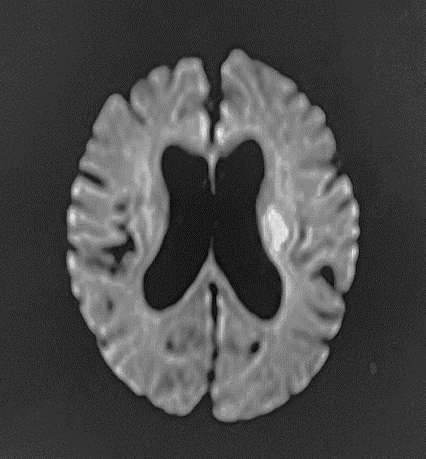

既に定評のある、脳神経、骨関節領域の他に、MRアンギオ(脳血管・四肢血管が描出可能)、MRCP(造影剤を用いない胆管・膵管画像)、急性期脳梗塞の診断(拡散強調像、MRアンギオや灌流画像を組み合わせることで治療方針の決定に有用)などの撮像法にも対応可能です。